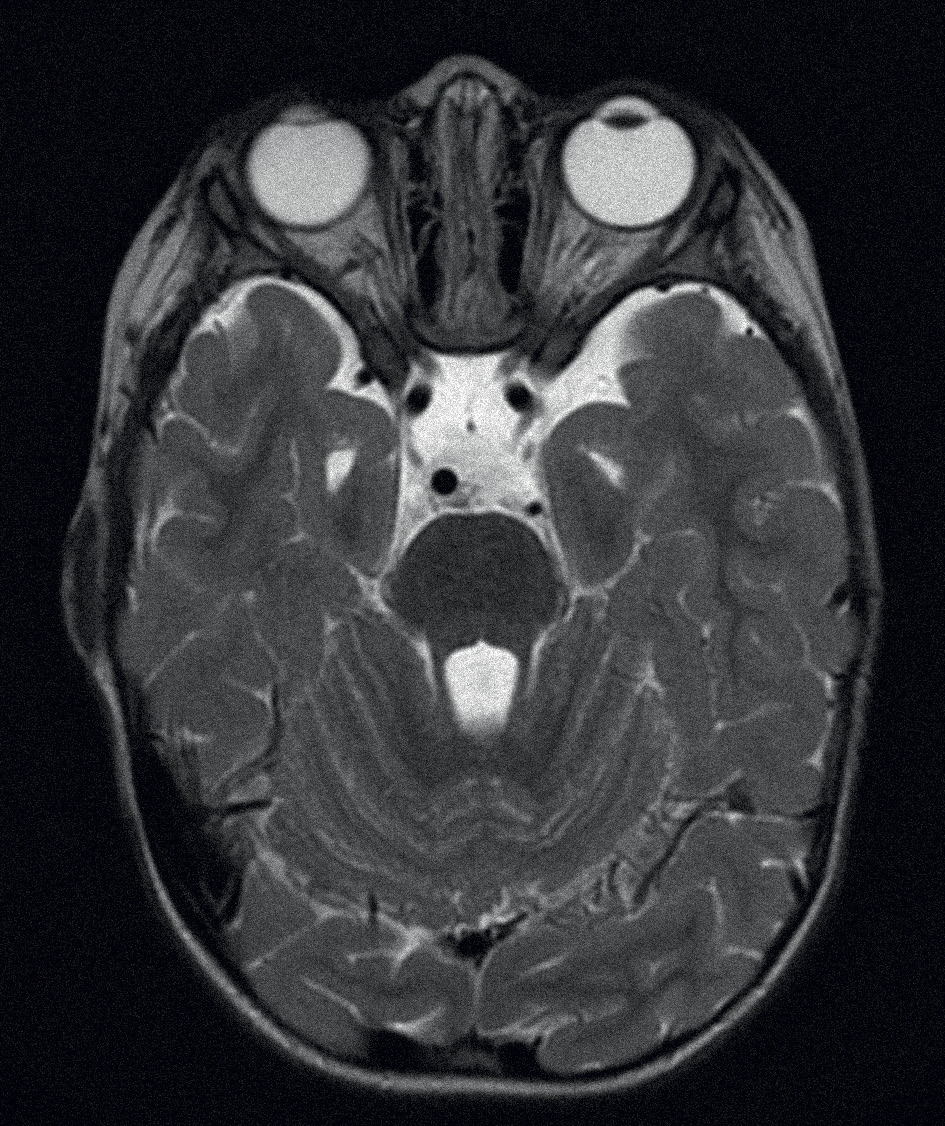

МРТ головного мозга: негрубое расширение субарахноидальных пространств височных отделов (больше слева) вследствие субатрофии, умеренное расширение селлярной цистерны (рис. 4). Заключение: негрубая субатрофия височных долей. МР-данных за очаговое поражение вещества мозга не получено.

Рис. 4. МРТ головного мозга пациентки с НПСПА.